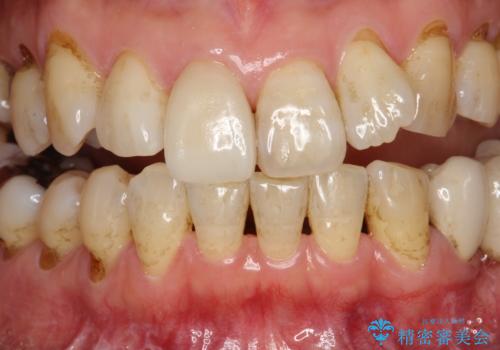

- 約2~3か月ごとに、定期的メンテナンスをしている方です。毎日紅茶をたくさん飲むとのことでステインを気にされ、クリーニング希望で来院されました。

全体的なチェックもかねてPMTC60分コースを行いました。

専門的な機械や材料を使用し、60分コースのPMTCクリーニングで、全体的な歯石や着色の除去を行いました。